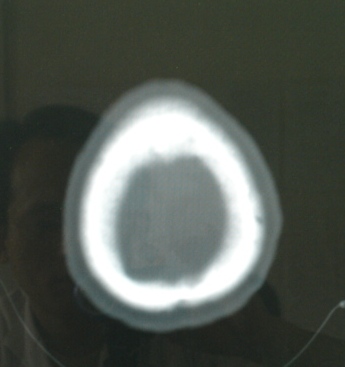

病人女性,58岁.左颞部外伤2小时,自觉头痛头晕.否认其它疾病史.

病灶ct值28~31hu.

左顶叶局限性脑水肿,可以考虑增强看看,排除肉芽肿,比如脑血吸虫病等。

局部脑沟有变化,建议强化,不除外血管畸形或转移性病变.

左顶叶不规则低密度灶后缘隐约见略高密度影,软化灶不能完全解释,建议增强检查或mai检查。

位置表浅 ct值28-31 建议增强或mr检查